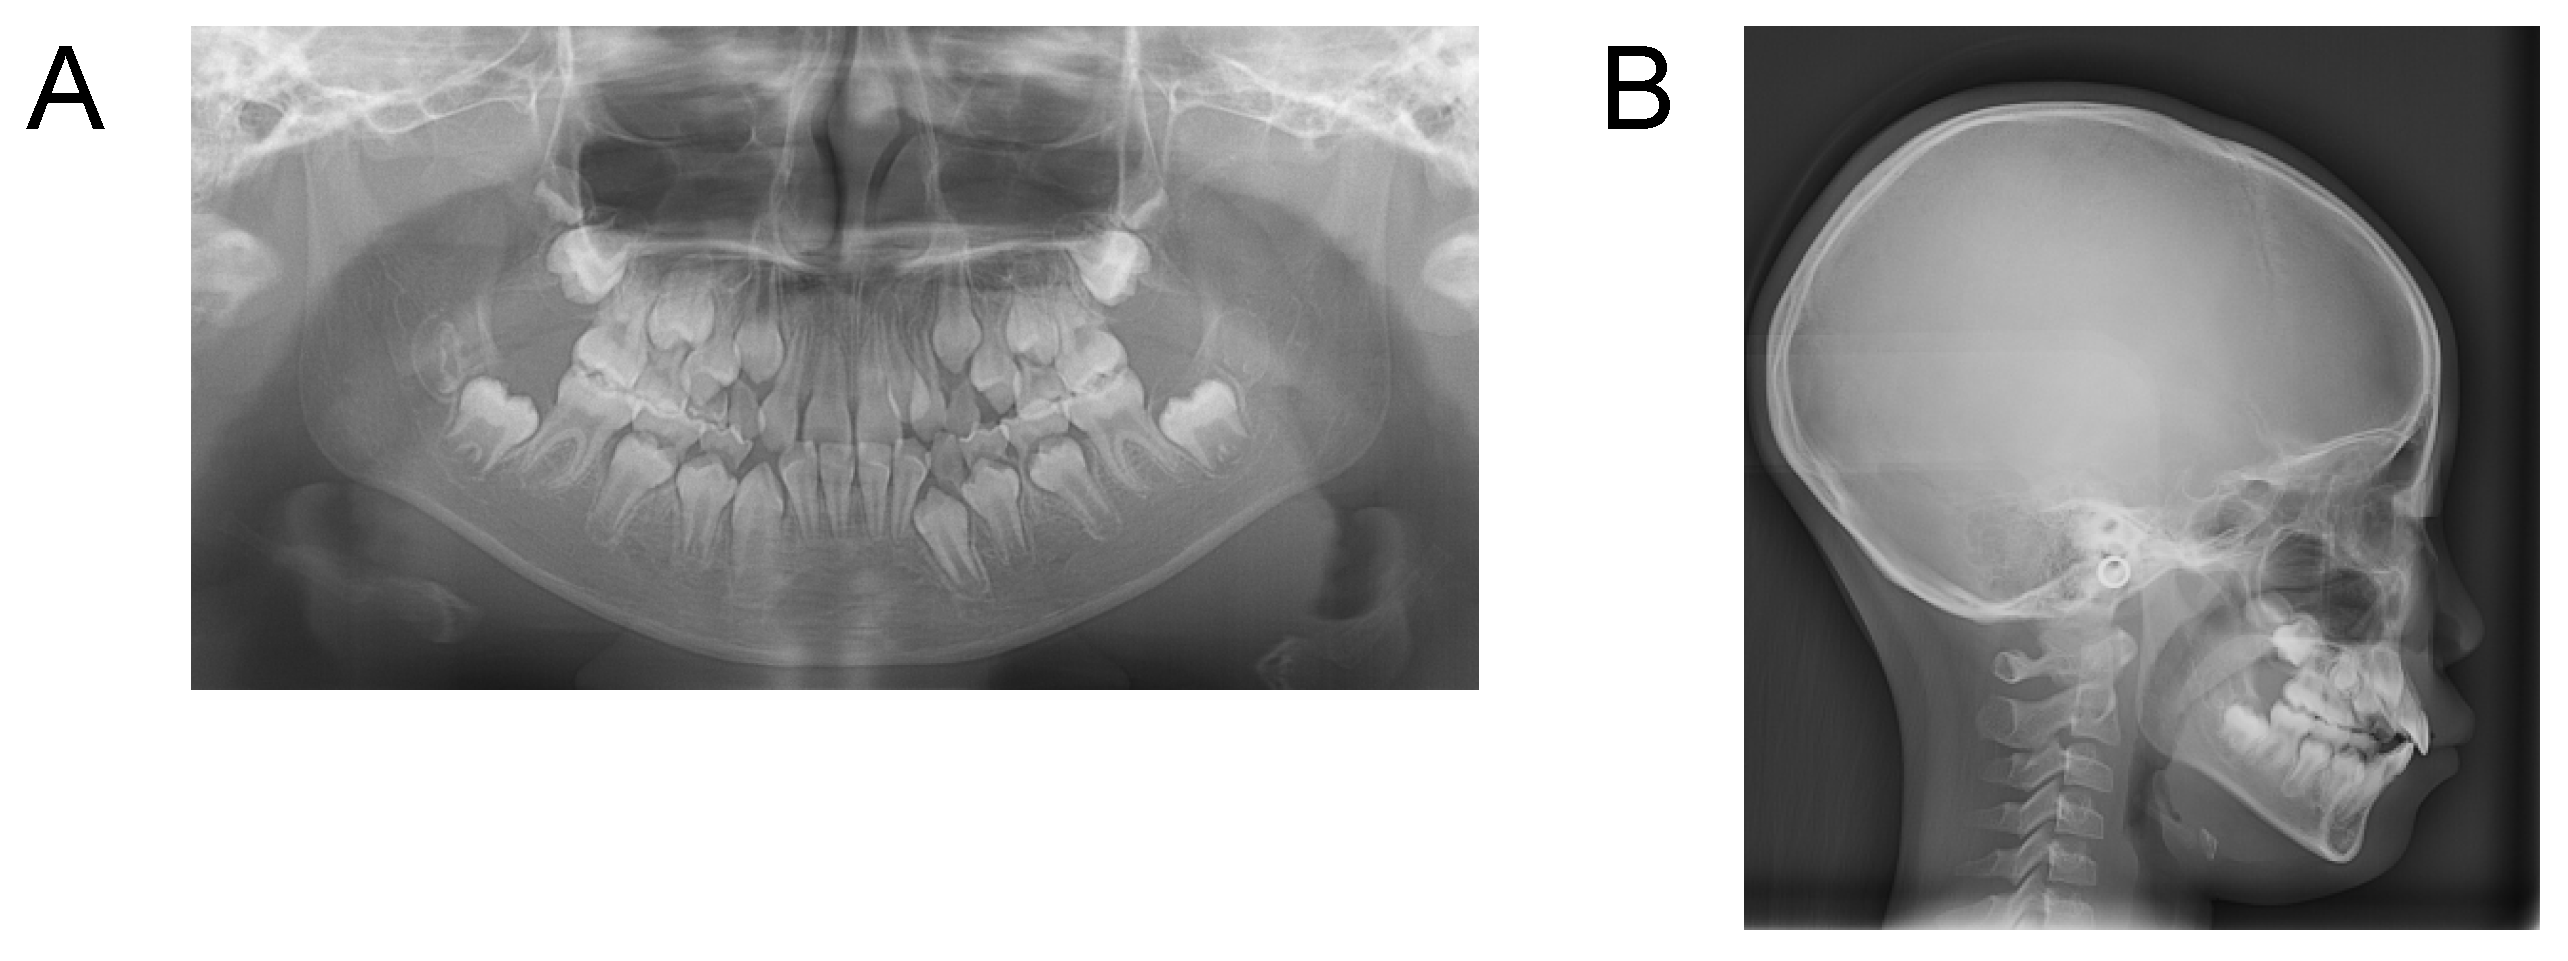

Case 1. Findings from initial examination